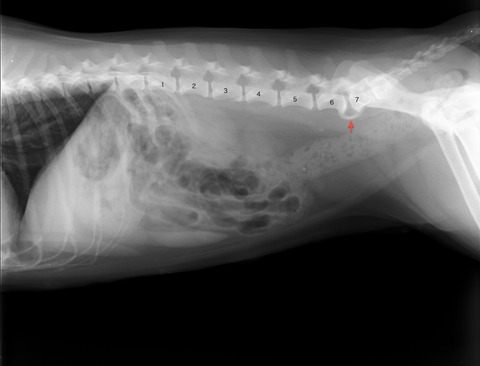

馬尾症候群

昨日は腰椎の仙椎化について紹介しました。

腰椎の仙椎化は様々な形態を示しますが

その不安定性から馬尾症候群および片側性股関節形成不全症を起こす事があるとされています。

このワンちゃんも第6-7腰椎間にブリッジ(赤矢印)が認められます。

今の所、馬尾症候群の症状はありませんが

今後注意が必要です。